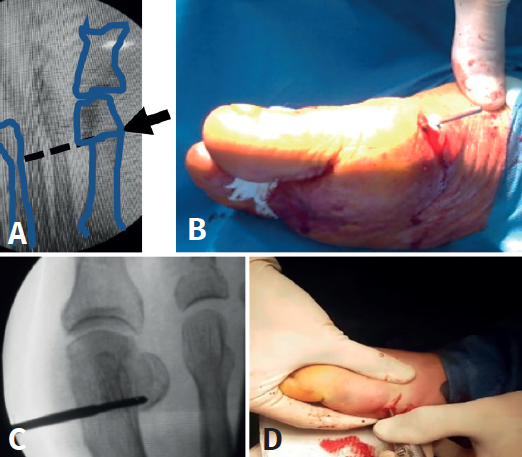

Mediante abordaje de 5 mm a nivel plantar proximal al bunion se realiza capsulotomía y exostectomía (Figuras 1A, B y C). Por otro abordaje de 3 mm realizado a 5 mm dorsal y distal del primero y a 15 o 20 mm proximal a la superficie articular (entre 7 y 10 mm del centro geométrico de la cabeza), extraarticular y equidistante a la cortical dorsal y plantar, se procede al tallado de la osteotomía de Chevron con fresa Isham larga (2,0 × 12 × 65 mm), (Figura 1D). Con la fresa dirigida, preferentemente, perpendicular al cuarto metatarsiano y llevándola ligeramente a plantar o dorsal según quisiéramos descender o elevar, respectivamente, la cabeza metatarsiana, perforamos el primer metatarsiano. En modelos sin fijación, elegimos esta dirección hacia proximal para lograr un leve acortamiento, que relaja la articulación metatarsofalángica y reduce las posibilidades de pérdida de corrección de la cabeza (Figura 2). En modelos con fijación se dirige más hacia distal, con referencia en la diáfisis del segundo metatarsiano o incluso perpendicular al primer rayo. Realizamos el corte dorsal casi vertical y el corte plantar lo más horizontal posible (paralelo al suelo), con dirección de distal a proximal, tratando de que esta rama sea más larga que la anterior. Se puede lograr de forma adicional corrección del DMAA. Una vez completa la osteotomía, se desplaza a lateral manualmente bajo visión radioscópica hasta que se logra una posición satisfactoria. No se coloca osteosíntesis. Se procede a la adición de otros gestos percutáneos de ser necesarios (liberación lateral de partes blandas, osteotomía de Akin, osteotomías de metatarsianos o dedos menores) (Figura 3).

Finalmente, limpieza capsular con raspa, control con intensificador, lavado, puntos de sutura si es necesario, dexametasona, vendaje de contención, zapato de suela rígida y apoyo inmediato completo.